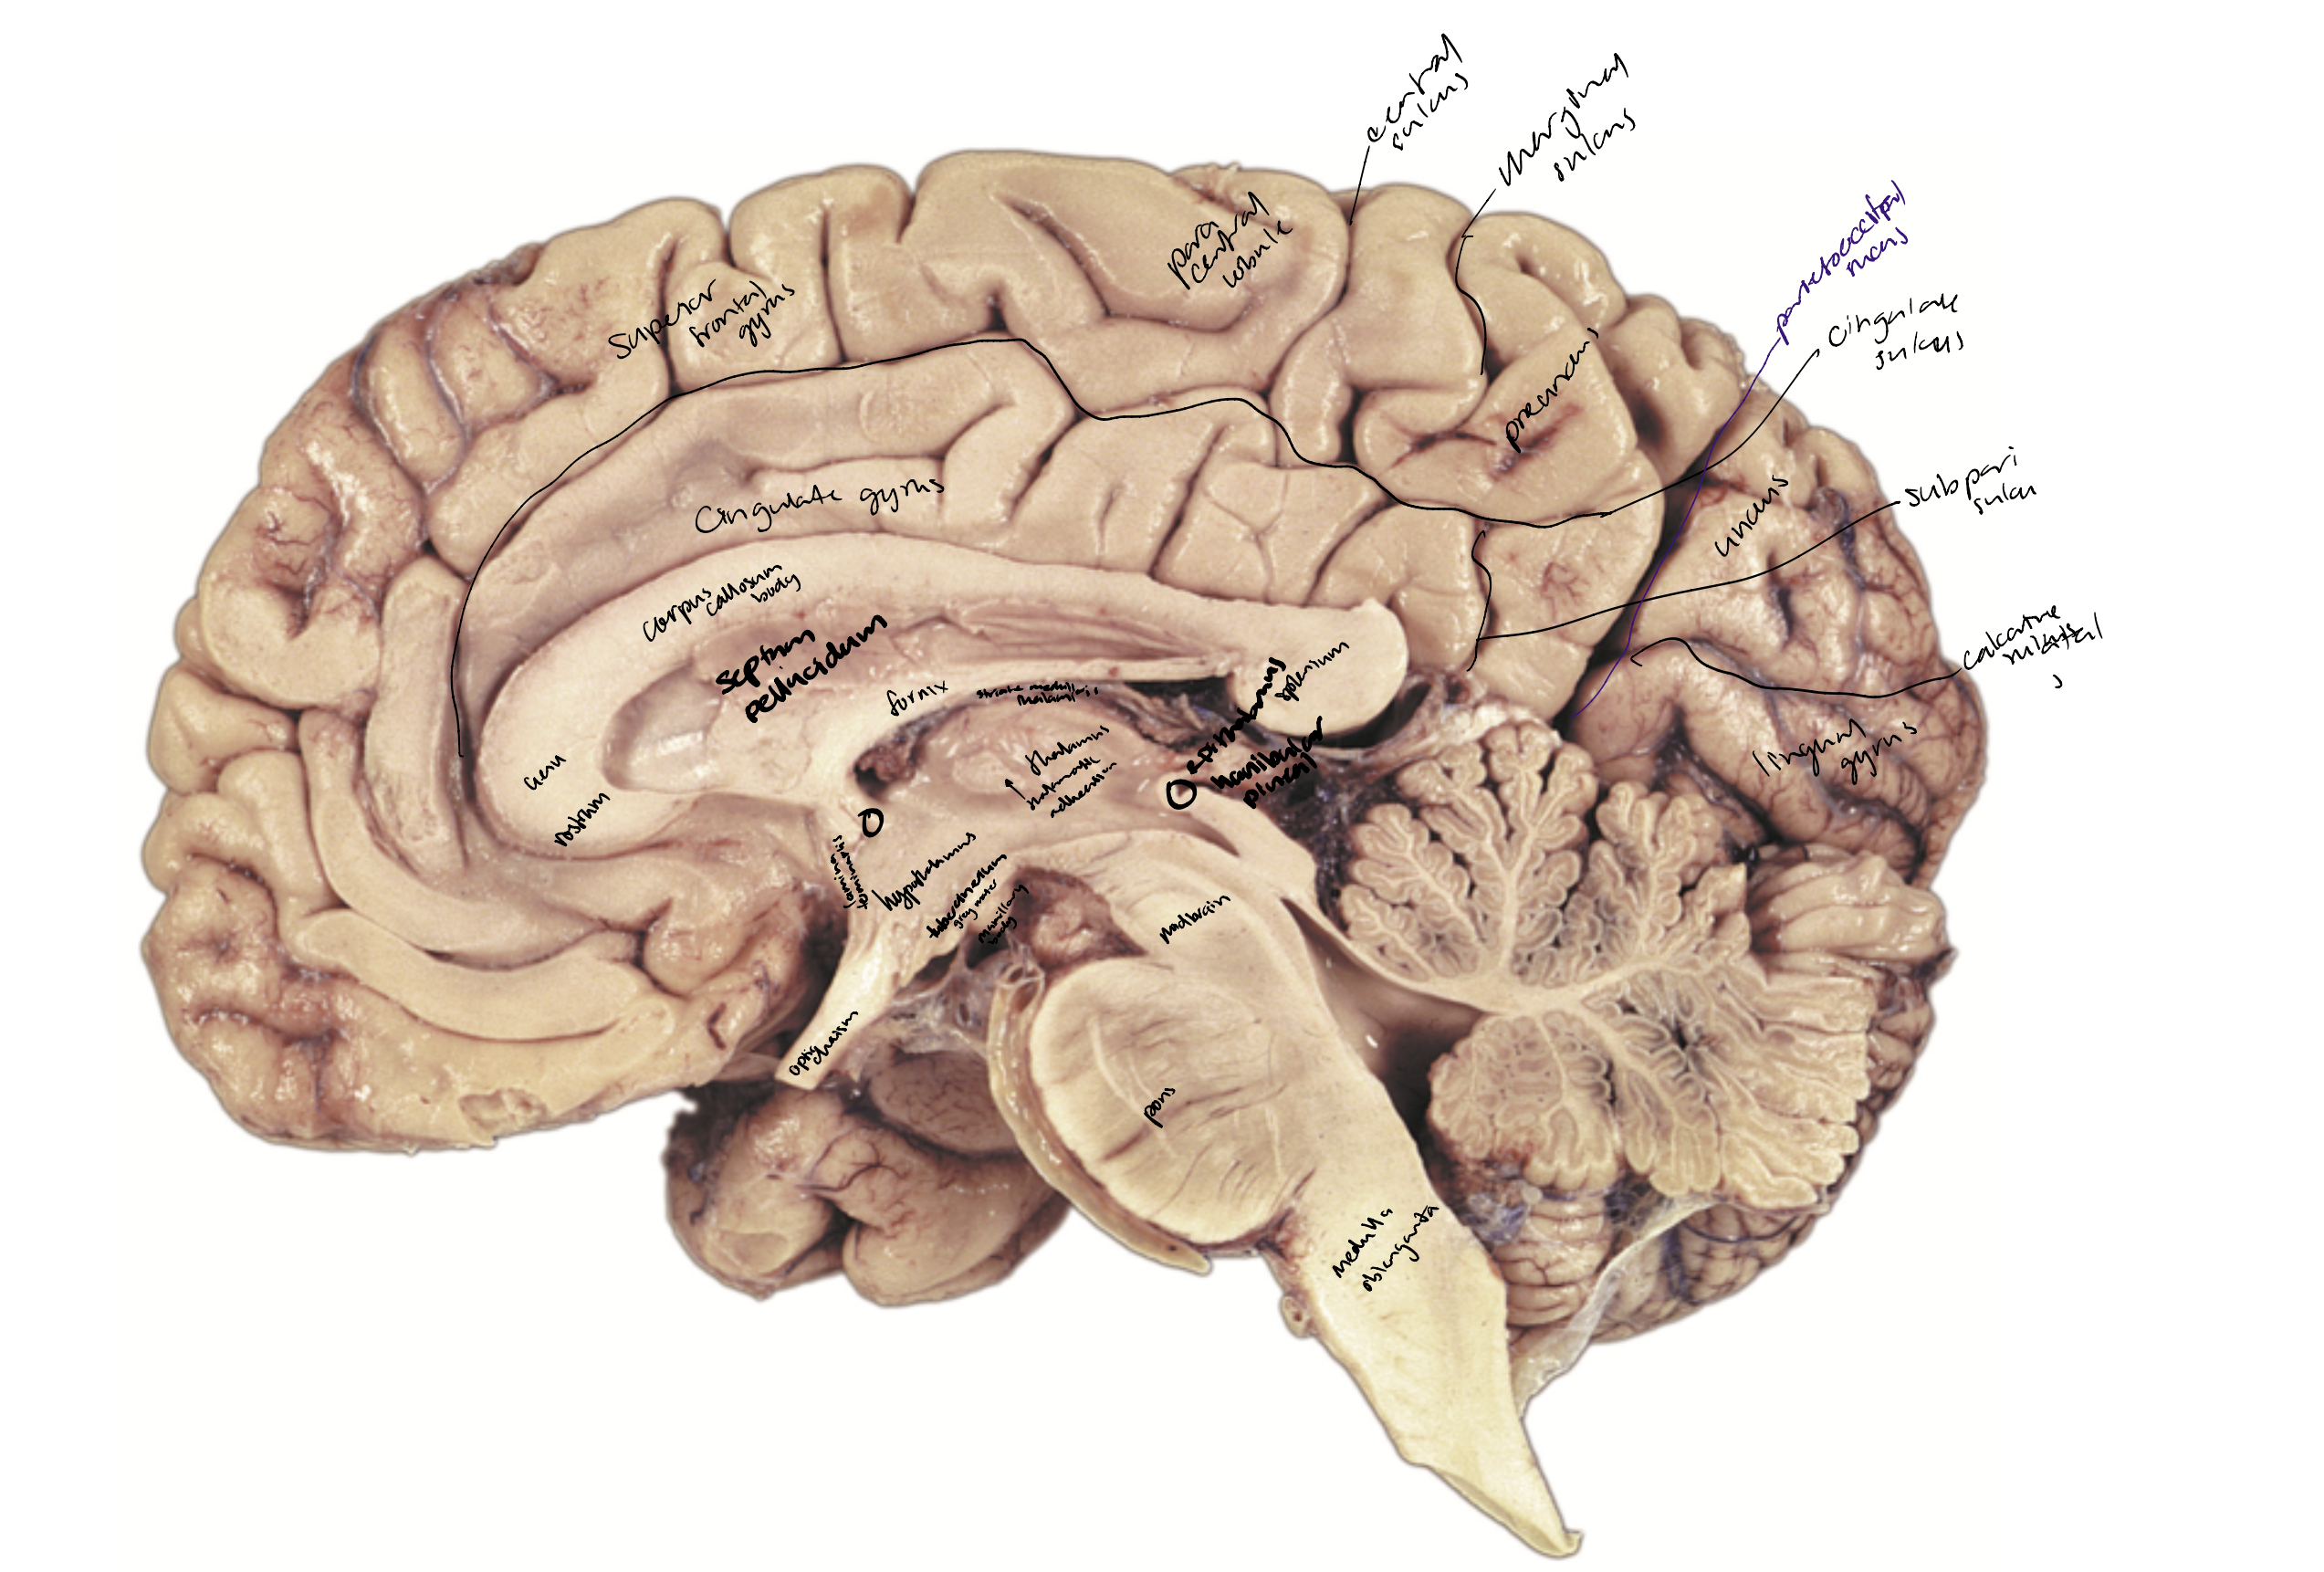

The cingulate gyrus

The callosal sulcus

The cingulate sulcus

The cingulate sulcus marginal branch

The subparietal sulcus

The calcarine sulcus

The parietooccipital sulcus

Posterior paracental lobule

Precuneus

Cuneus

Lingual gyrus

Collateral sulcus

The occipitotemporal gyrus

Hypothalamus

Anterior commissure

Lamina terminalis

Thalamus

Optic chiasm

Infundibulum and pituitary gland

Tuber cinereum

Mammillary bodies

Cingulate gyrus

Fornix

Striae medullaris thalami

Pineal gland

Posterior commissure